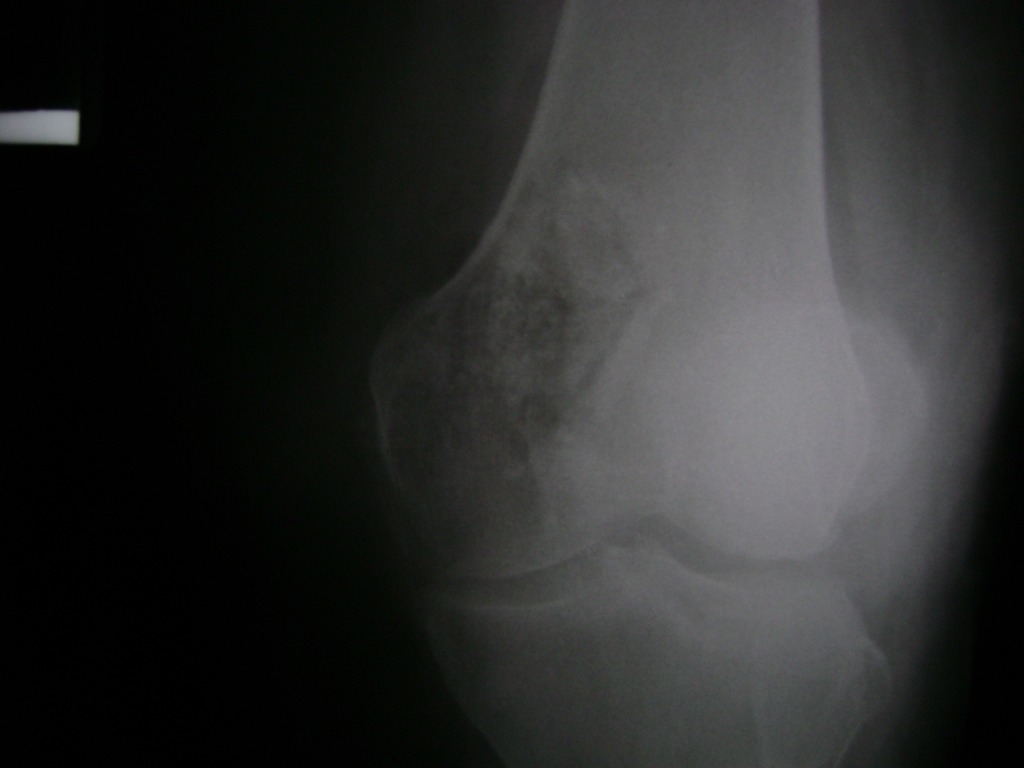

Cirugías de Codo - Rodilla

La artroscopia de rodilla es un cirugía en el cual la estructura interna de la articulación es examinada ya sea para realizar un diagnostico o para realizar un tratamiento, este procedimiento se realiza utilizando un instrumento parecido a un pequeño tubo llamado artroscopio.